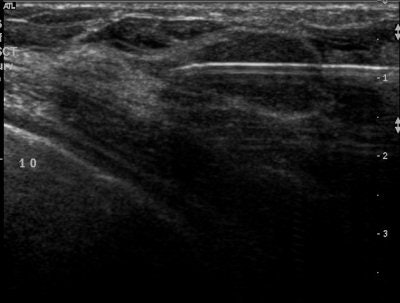

| Above, placement of cryoablation needle in the fibroadenoma. Middle, the ice ball forms at tip of cryoablation needle. Below, an illustration of ultrasound visualization of the ice ball. Images courtesy of Galil Medical. |

This method of destroying diseased tissue by applying cycles of freezing and thawing temperatures has been most commonly used for the treatment of renal tumors, prostate cancer, and endometriosis. For breast fibroadenoma, ultrasound is used to guide the cryoprobe, through which argon gas flows, and an ice ball forms at the tip engorging and then freezing the tumor.